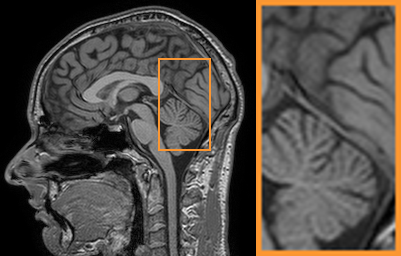

| Ground Truth (PSNR) | Zero-filling (22.33) | TV (25.22) | SIDWT (25.10) | PBDW (27.39) | |

|

|

|

|

|

|

| PANO (28.77) | FDLCP (29.78) | ADMM-Net (27.91) | BM3D-MRI (29.35) | Ours (30.48) |

| Ground Truth (PSNR) | PANO (27.73) | FDLCP (26.84) | BM3D-MRI (26.27) | Ours (28.22) |

First, we test on 25 T1-weighted MRI data using three different undersampling patterns with a fixed 10% sampling rate. Fig. 3 shows the quantitative results (PSNR). Our method performances best for all three cases and has stronger stability compared with the second best method on variance. As for the effect of sampling ratios variation, we use radial mask under 10%, 30% and 50% sampling rates with evaluation of RLNE and MSE. Fig. 4 shows that our method has the lowest reconstruction error for all sampling rates. For more intuitive comparison, we illustrate the reconstruction error in term of pixels in Fig. 5. We also offer the qualitative comparison in Fig. 6. Visualized results demonstrate our method has better performance in both artifacts removing and details restoration. Time consuming is also considered. We compare our method with others on the 25 T1-weighted data using Radial mask with 10% and 50% sampling rate. Notice that ADMM-Net and ours are tested on GPU for the incorporation of deep architecture. Tab. 1 shows that our method provides an efficient reconstruction process and comes to the fastest method among the state-of-the-art competitors.